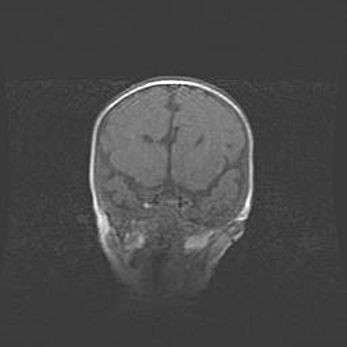

Мальформация Денди-Уокера. Киста задней черепной ямки.

Агенезия мозолистого тела.

Возраст: 2,5 месяца

Вес: 2420 г

Пол: женский

Окружность головы: 37 см

Срок гестации: 32 недели

Мальформация Денди—Уокера — редкий вид патологии ЦНС, представляющий собой врожденный порок развития каудального отдела ствола и червя мозжечка, ведущий к неполному раскрытию срединной (Мажанди) и латеральных (Лушка) апертур IV желудочка мозга. Для этогно синдрома характерна триада симптомов: гипотрофия червя мозжечка и/или полушарий мозжечка, кисты задней черепной ямки, гидроцефалия различной степени. В 70% случаев порок сочетается и с другими аномалиями головного мозга, в частности с агенезией мозолистого тела.